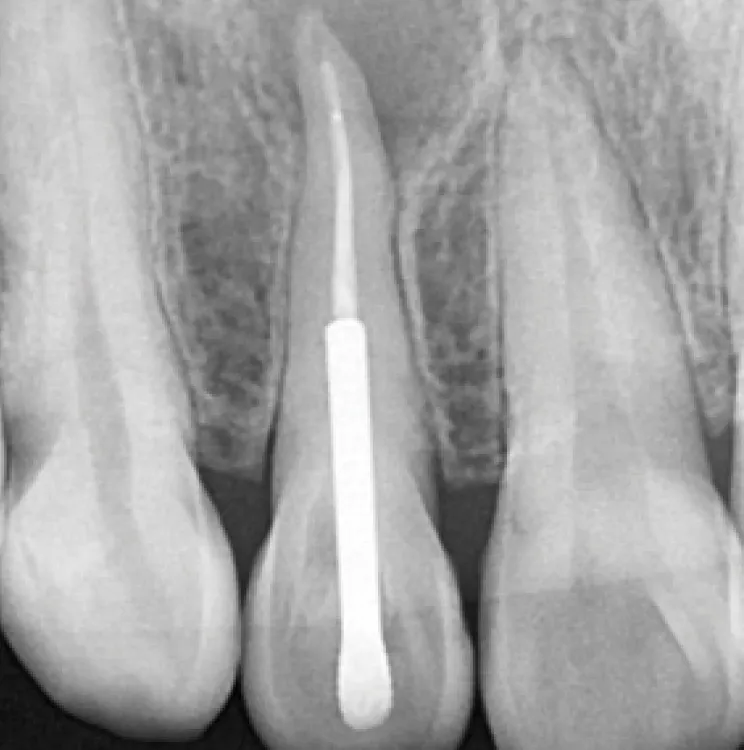

3

3 mois plus tard